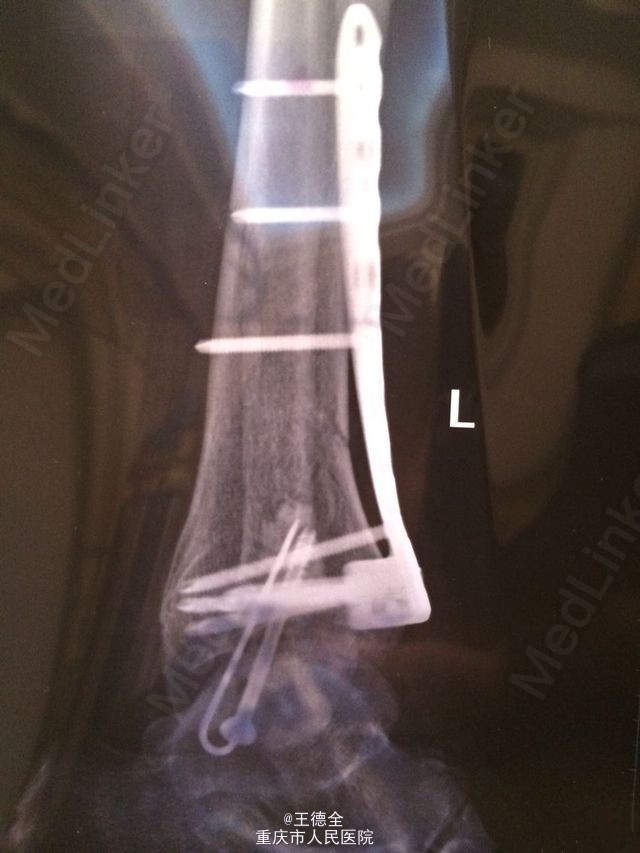

左脚pilon骨折一例

患者老年男性,高出摔落伤,查体:左踝部中度肿胀,畸形,压痛,活动受限,足背动脉波动好,足趾运动及末梢血运、感觉正常。